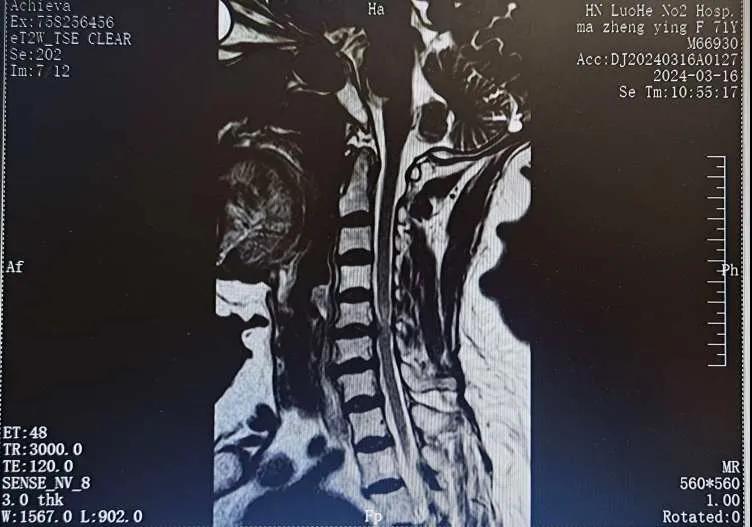

近日,70歲的馬阿姨,因摔傷后出現(xiàn)持續(xù)性頸部疼痛伴右側(cè)肢體無力、麻痛,影響日常生活。于是來到市二院神經(jīng)外科就診,經(jīng)檢查發(fā)現(xiàn):頸椎MR示:頸3/4、4/5、5/6、6/7椎間盤變性突出(中央型)并繼發(fā)性椎管變窄,頸椎退行性改變,頸5椎體水平頸髓水腫。神經(jīng)外科副主任劉沛濤根據(jù)患者癥狀、體征、影像學(xué)三者結(jié)合診斷為“脊髓型頸椎病”,考慮到患者癥狀逐漸加重、保守治療效果不佳等情況,建議盡快手術(shù)治療。